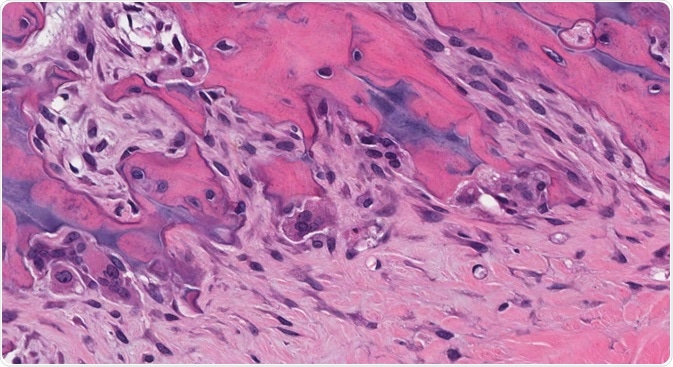

Credit: vetpathologist/Shutterstock.com